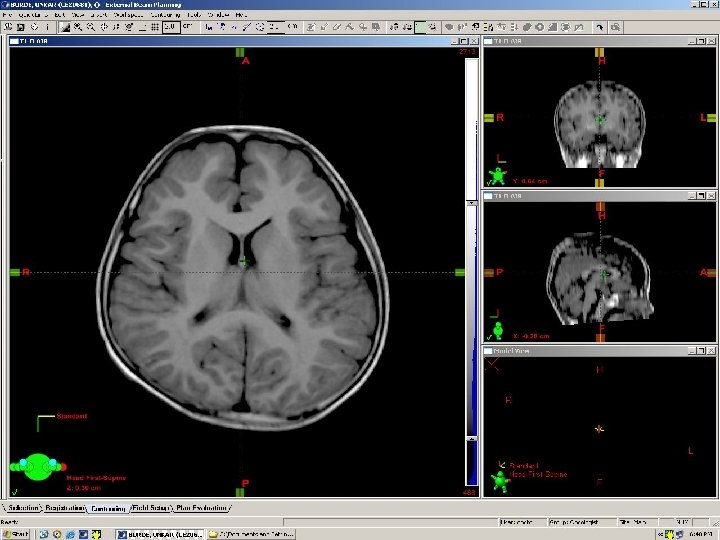

Middle Frontal Gyrus Cingulate gyrus Corpus callosum Inf Frontal Gyrus Insular cortex Septum pellucidum 3 rd Ventricle Sup temporal gyrus Inf Temporal Gyrus hippocampus Internal Carotid A

# Frontal Lobe Falx cerebri Caudate Thalamus & 3 rd Ventricle Putamen Choroid plexus 4 th Ventricle Splenium of corpus callosum